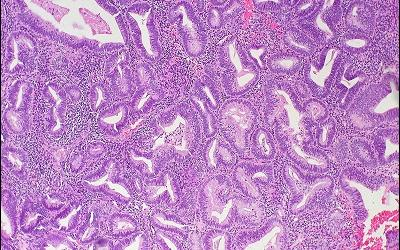

Гиперплазия — увеличение количества клеток в органе или ткани, ведущее к увеличению размеров органа или ткани. Гипертрофия и гиперплазия — разные процессы, но часто они сопровождают друг друга и могут быть инициированы одними и теми же внешними стимулами. Гиперплазия развивается в органах и тканях, где клетки способны к делению, т.е. к увеличению своего количества. Гиперплазия может быть физиологической и патологической. Физиологическая гиперплазия

Физиологическую гиперплазию подразделяют на: гормональную гиперплазию, которая при необходимости увеличивает способность ткани выполнять большую функциональную нагрузку; компенсаторную гиперплазию, которая обеспечивает увеличение массы ткани после повреждения или частичного удаления. Пролиферация железистого эпителия женских молочных желез в пубертатном периоде и во время беременности, которая часто сопровождается гипертрофией клеток железистого эпителия, — яркий пример гормональной гиперплазии. Классический пример компенсаторной гиперпла